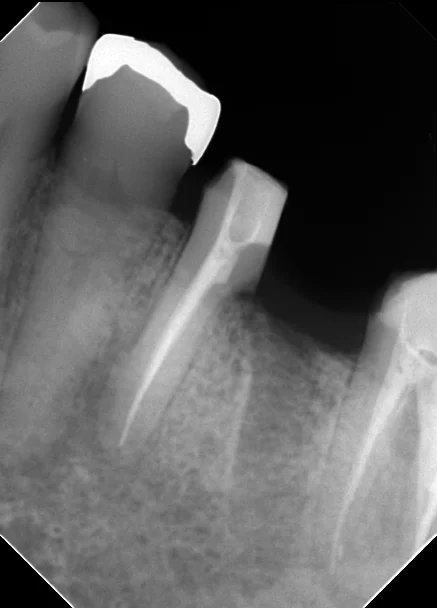

今回の場合も2本の根の管があるように最初のレントゲン上では写っていましたが、実際にはその2本は非常に細い道でつながっており、しかも元々の根の管がその細い道の中に隠れていました。

最初のレントゲンに比べると神経の治療後の薬が根の先まで綺麗に入っているのが分かるかと思います。

無事に神経の治療も終わり、後ろの根の抜歯後の傷も問題なく治ったため、最終的な被せ物に移行することとなりました。